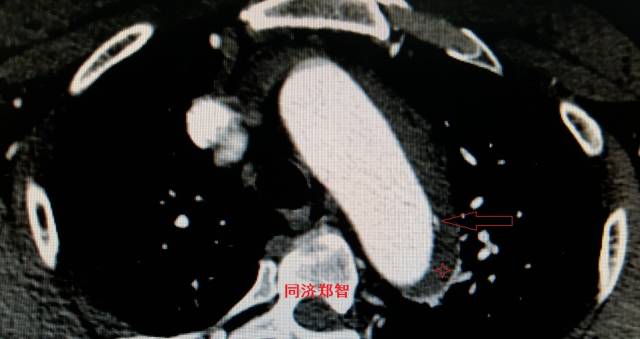

平扫CT提示主动脉弓层面及右肺动脉层面均可见主动脉血管腔内的内膜片影(红色箭头所示),CTA显示为A型主动脉夹层。

图8-11